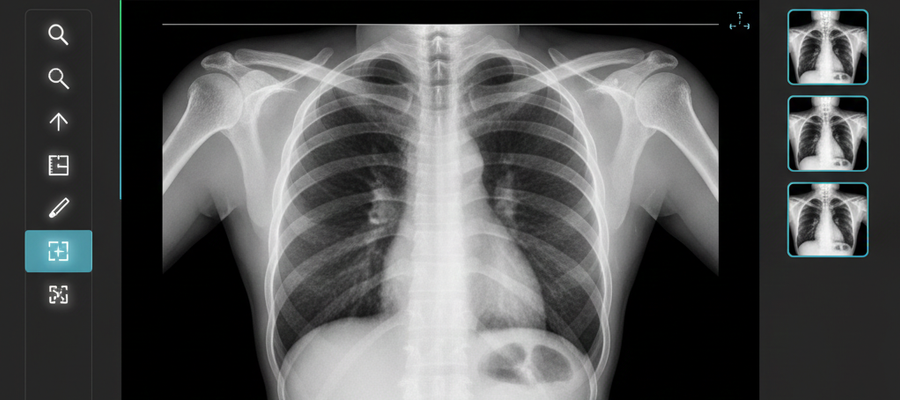

In modern medicine, images do more than show anatomy — they provide answers. X-rays, CT scans, MRIs, and ultrasounds contain critical diagnostic information. This data is stored in a special format called DICOM (Digital Imaging and Communications in Medicine).

A DICOM viewer is the tool that unlocks this information. Knowing how to use it correctly is no longer optional. It is essential for accuracy, confidence, and speed in clinical decision-making.

A DICOM viewer is software that allows you to open, view, analyze, and manipulate medical images stored in the DICOM format.